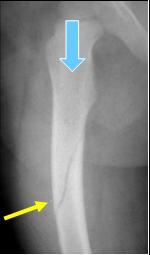

Oblique fracture

n Force applied in

same direction as

long axis of bone